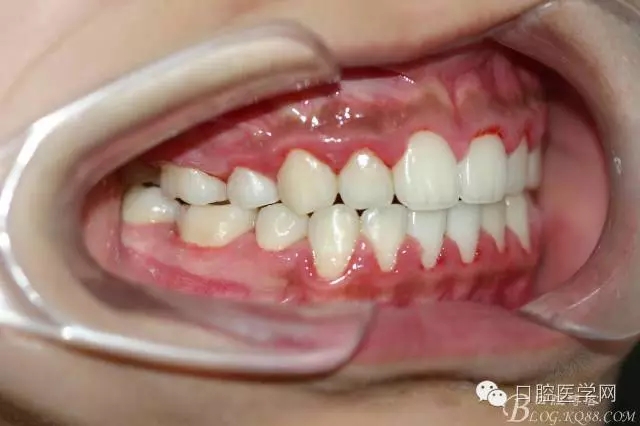

正畸查:替牙合。第一恒磨牙中性合。上牙弓尖圓型下牙弓方圓型。前牙覆合3度覆蓋7.5mm。下前牙咬到上舌側(cè)牙齦。上頜擁擠4.0mm,下頜擁擠

3.0mm。上頜稍前突下頜后縮,上下唇前突,上前牙覆蓋下唇,下唇外翻。面下三分之一過(guò)短,頦唇溝明顯,開(kāi)唇露齒,頦饜窩明顯。顳下頜關(guān)節(jié)開(kāi)閉口無(wú)彈響,無(wú)壓痛,開(kāi)口型開(kāi)口度正常。

正畸前照片: